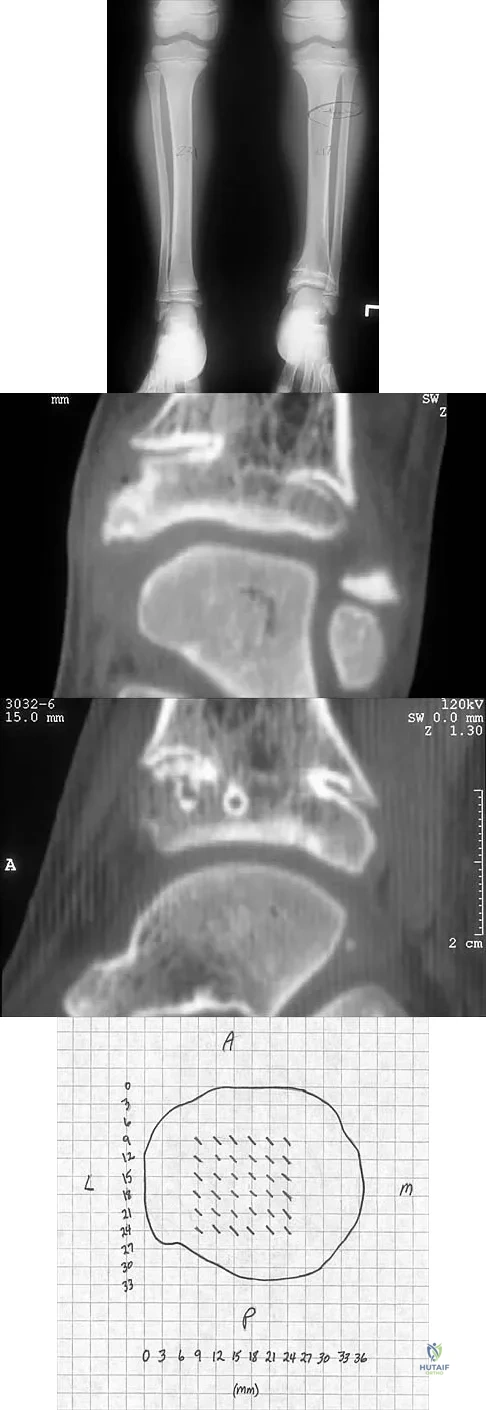

Question 71

A 5-year-old girl sustained a comminuted Salter-Harris type IV fracture of the left distal tibia 2 years ago. The AP radiograph shown in Figure 54a reveals a growth arrest and a 1.4-cm limb-length discrepancy. The ankle is in approximately 20 degrees of varus. Figure 54b shows a coronal reconstruction image of the distal tibial physis, and Figure 54c shows a sagittal reconstruction image of the same area. On the sagittal reconstruction image, the bar extends from the 9-mm mark to the 24-mm mark in 3-mm increments. On the coronal image, the bar extends from the 9-mm mark to the 24-mm mark, also in 3-mm increments. A map of the physeal bar based on these measurements is shown in Figure 54d. Initial treatment should consist of

Explanation